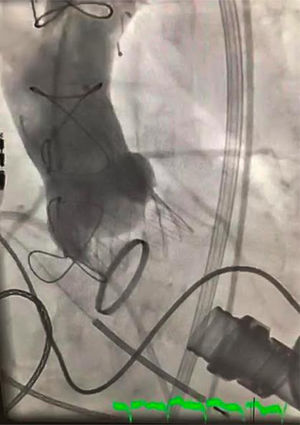

El implante fue un éxito, pasando de una IA severa (fig. 1) a una insuficiencia aórtica mínima (fig. 2) por aortografía y sin gradiente transvalvular.